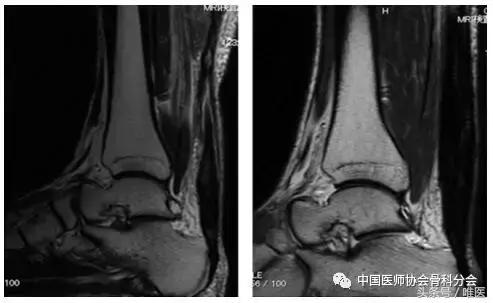

在术前T2加权图像中,在22例患者中观察到肌腱状肌腱增厚和腱内弥漫性高信号改变,但这些患者术后6个月MRI在MRI腱上有均匀的低信号改变(图3)。在其余8名患者中观察到肌腱变薄。在这8例患者中的6例中,术前观察到弥漫性腱内高信号变化。但术后6个月在MRI中可见肌腱形腱增厚和均质的低信号改变(图4)。

图3:一个34岁女性肌腱的T2加权磁共振成像显示梭形肌腱增厚。左:术前图像显示损伤后4个月的弥漫性腱内高信号改变。右:术后6个月图像显示均匀的低信号改变。